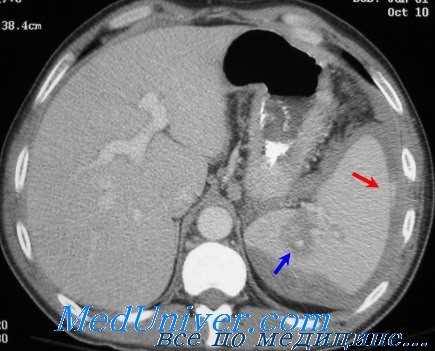

(Слева) На аксиальной КТ с контрастным усилением у женщины 39 лет, получившей множественные травмы в ДТП, в селезенке определяются многочисленные участки вытянутой и неправильной формы, не накапливающие контраст.

(Справа) На аксиальной КТ с контрастом у этой же пациентки (типичный случай разрыва селезенки) также определяются участки пониженного накопления контраста в селезенке, визуализируется небольшая гематома возле ее края.